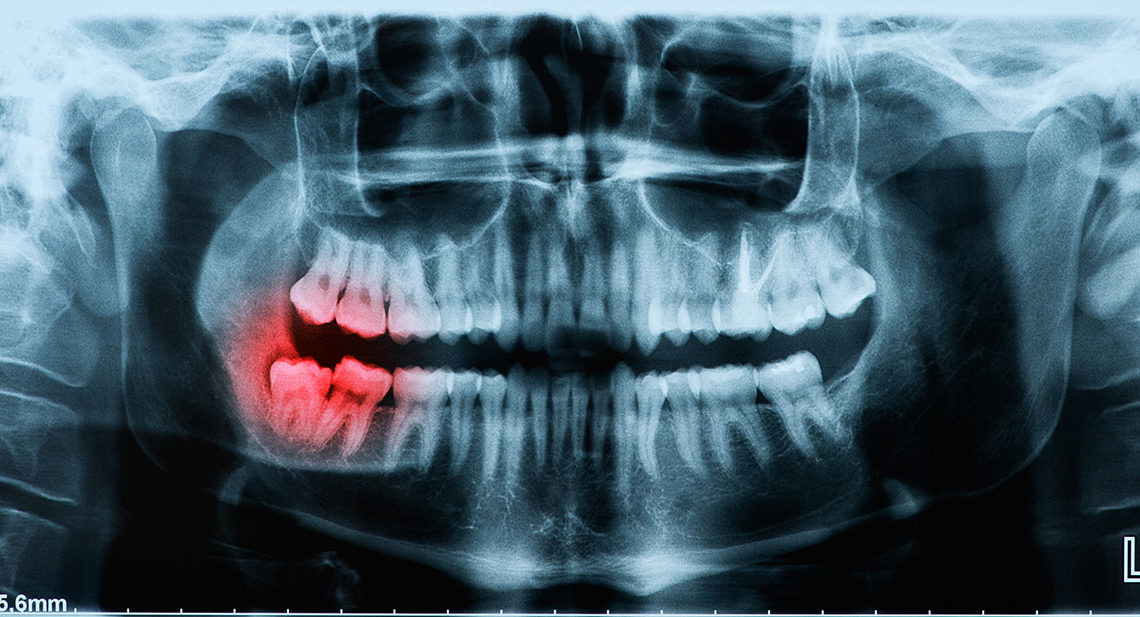

Why Do Wisdom Teeth Break?

As wisdom teeth are the last to come through, there may be limited space in your mouth. As they try to erupt through your gum, another tooth may already be occupying the same spot. Your wisdom tooth may come through at an unnatural angle, or even crack as it forces its way out.

Wisdom teeth may be more likely to break than your other teeth if they have not erupted correctly. You may find it more challenging to use those teeth to chew, and there is a greater chance of decay if it is harder to clean thoroughly around that area.

As with any other tooth, your wisdom teeth are susceptible to blunt force trauma, such as an impact on your jaw, or biting into something hard. If your teeth crack, or fragments of your wisdom tooth break off, this is likely to cause discomfort.

Risks from Having a Broken Wisdom Tooth

Bacteria can thrive in gaps where bits of the tooth broke. A gap in a wisdom tooth is a hospitable environment for an infection and a weak point in the tooth.

Additionally, a broken or cracked wisdom tooth puts the entire tooth’s health at risk. Bacteria can invade the tooth and infect the dental pulp. In those cases, the tooth must either be extracted or given a root canal treatment. In most cases, it’s better just to remove the tooth.

It is essential to see your dentist quickly if you have a broken wisdom tooth. Your dentist will carry out an assessment and tell you if you should have a wisdom tooth extraction.

Although it is possible to fill a broken tooth, or repair it using a crown, you will want to consider removing your wisdom tooth. Wisdom teeth usually do not bring any real benefits to your mouth, but they can increase the chances of breakages and infections.

If you need to have your wisdom teeth removed, your dentist can perform the procedure in just one visit. Depending on how your tooth has erupted through the gums and sits in the jawbone, you may need a simple or complex extraction.

In a simple extraction, your dentist numbs the area around the tooth and using a rocking motion, loosens the tooth from its socket. In a complex extraction, you may require general anesthesia or conscious sedation, especially if you are an anxious patient.

Your dentist makes an incision in the gum line and breaks the tooth into sections, removing the pieces. After the extraction, your dentist places a piece of gauze over the site to stem the bleeding and may use sutures. Bring a chaperon to drive you home, as the sedation’s effects can last in the body for a few hours after your procedure.